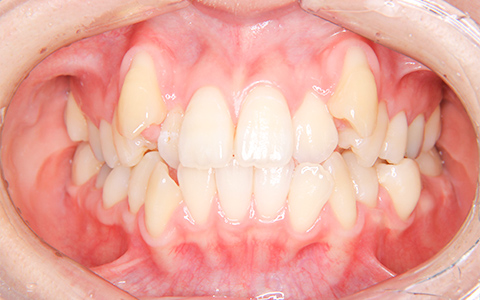

治療前

治療後

施術内容 ガタガタな歯並びのご相談でご来院(小児矯正時7歳 成人矯正時13歳)。叢生に対して、小児矯正(固定式拡大装置、セクショナルワイヤー)から成人矯正(マウスピース型矯正装置)に移行して対応した非抜歯治療

治療期間 小児矯正:1年7ヵ月、成人矯正:1年(通院23回)

費用 小児矯正:440,000円、成人矯正:480,000円

リスク・副作用 歯が動く痛み、歯髄壊死、歯根吸収、歯肉退縮、リテーナーを使用しないことによる後戻り